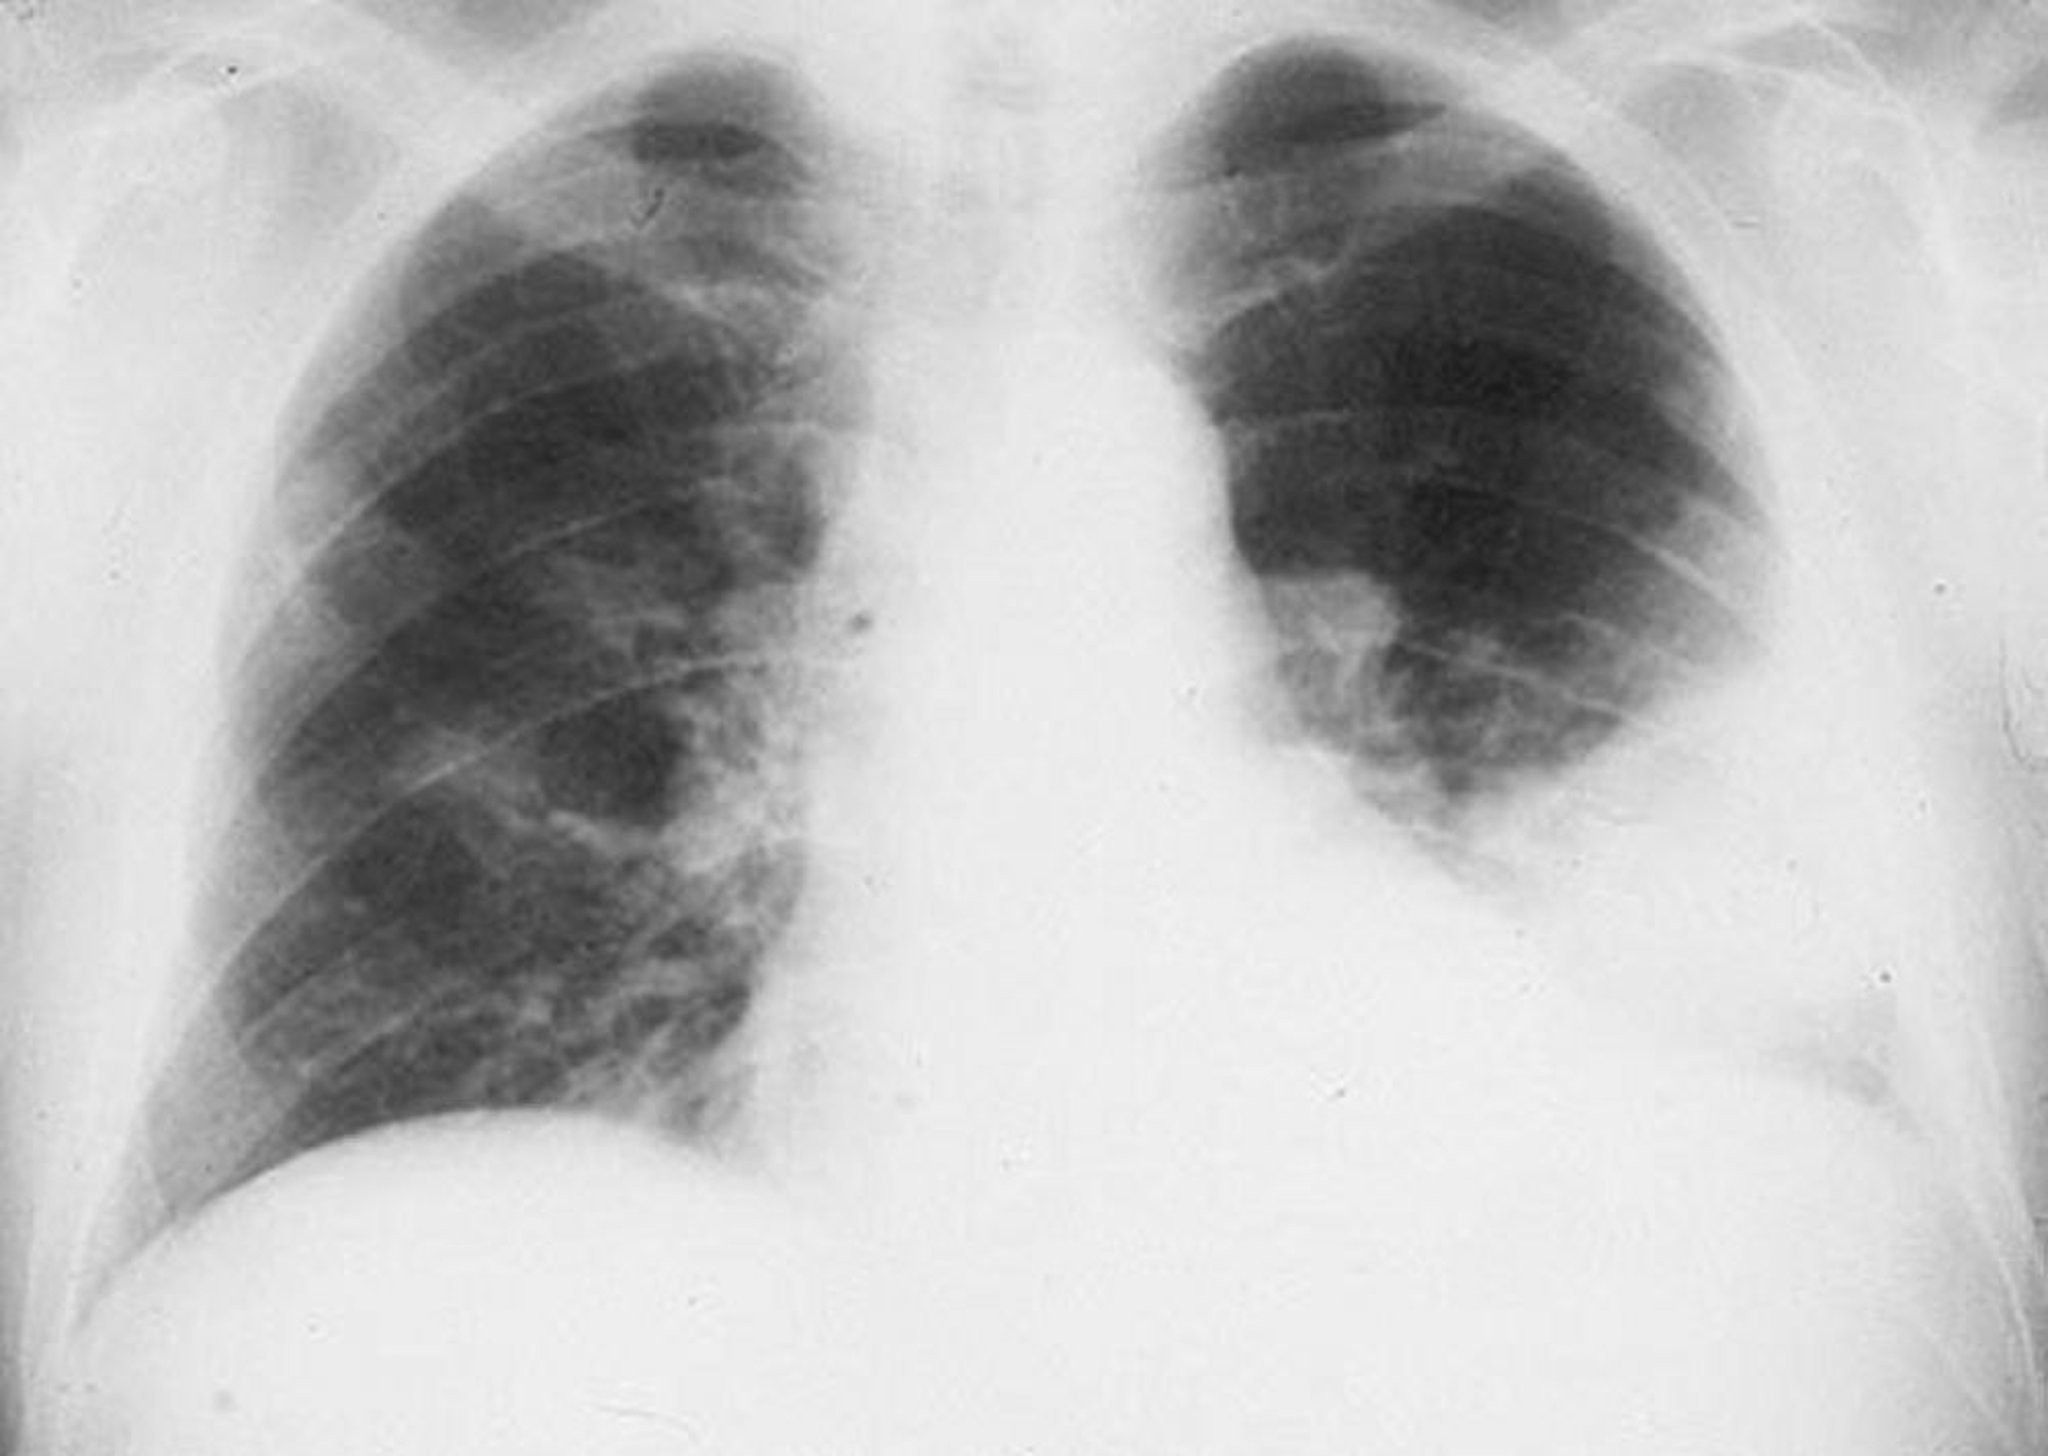

左下葉の浸潤影

細菌性肺炎の男性における左下葉の肺胞浸潤影。